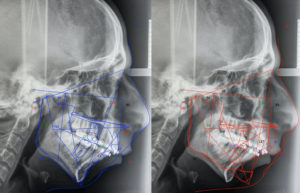

• Orthognathic Surgery / Corrective Dentofacial Deformity